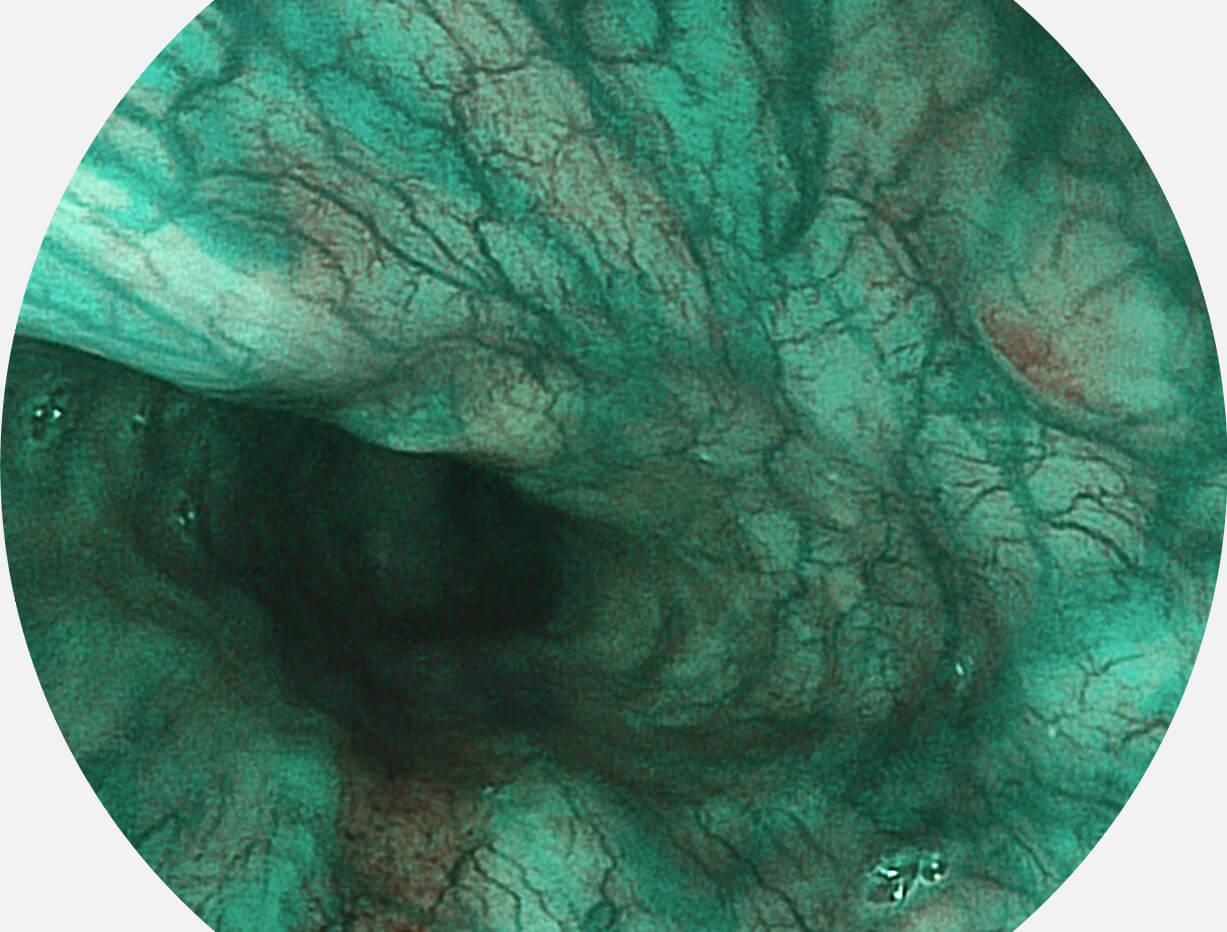

Spectral Focused lmaging, SFI

图像具有高亮度、高黏膜血管颜色对比度的特点,且不改变粘液、食物残渣、粪便的基本颜色,可在中远景下进行观察,助力消化道早期疾病的诊断。

SFI图像

采用光路合束技术,光谱自由度高,实现了更丰富的照明模式,染色模式SFI及VIST,从远景到近景,助力消化道早期疾病诊断。